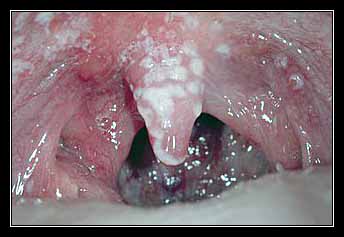

Cũng có thể đau nhiều hơn nếu như bạn nuốt hoặc nói chuyện. Họng hay amidal của bạn cũng có thể ửng đỏ lên.

Đôi khi, một mảng trắng hoặc một khoảng trắng có mủ sẽ hình thành trên amidal. Mảng trắng thường do nhiễm vi khuẩn Streptococcus hầu họng hơn là do nhiễm virus hầu họng.